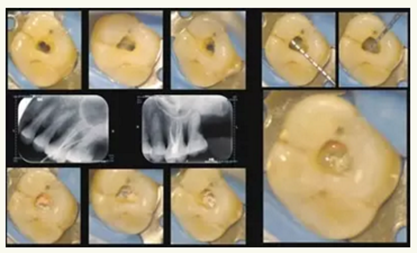

根管治療是目前牙髓病與根尖周病最有效的治療方式,所謂根管治療是在牙體表面切割獲得進(jìn)入髓腔的通道,并由此進(jìn)入牙齒內(nèi)部的根管空間,采用手術(shù)的方式清除感染病灶,并用惰性材料對(duì)根管進(jìn)行嚴(yán)密的充填以消除死腔。在國(guó)家臨床重點(diǎn)??频慕ㄔO(shè)下,牙體牙髓科建立起了顯微牙髓治療的亞???,目前已擁有12臺(tái)根管顯微鏡,在手術(shù)放大設(shè)備的幫助下,微創(chuàng)治療已成為可能。日常治療過程中,醫(yī)師無需磨除過多的牙體組織,即可獲得牙髓治療的入路,從而保留了更多的牙體組織,使牙齒的抗力進(jìn)一步得到增強(qiáng)。

在根管顯微鏡的幫助下,醫(yī)師對(duì)于根管的解剖結(jié)構(gòu)將更為明確,顯微根管治療器械將有助于醫(yī)師更徹底的清除根管內(nèi)的感染,使根管治療成功率進(jìn)一步提高,同時(shí)對(duì)于器械分離,根管壁破壞等手術(shù)并發(fā)癥也能得到有效的控制。

▲顯微牙髓治療